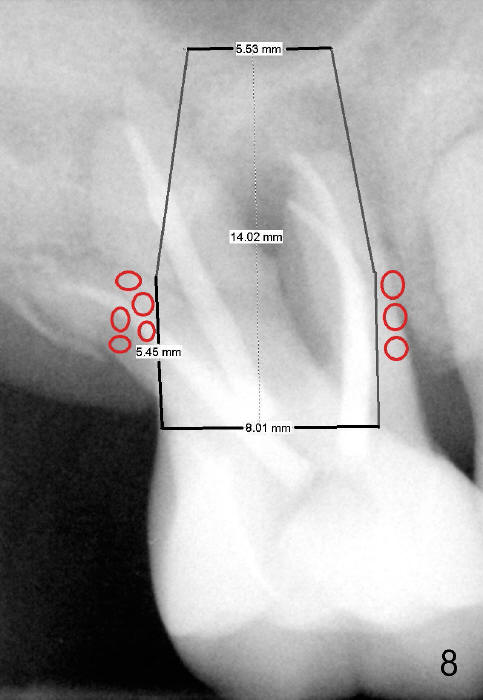

If primary stability is questionable with the bone-level implants mentioned above, a 7x14 mm gingiva-level implant will be the next alternative (Fig.7). If primary stability is still insufficient, a 7x17 mm (with sinus lift) or 8x14 or 17 mm will be placed (Fig.8). The larger the implant, the less bone graft is used (compare Fig.7,8).